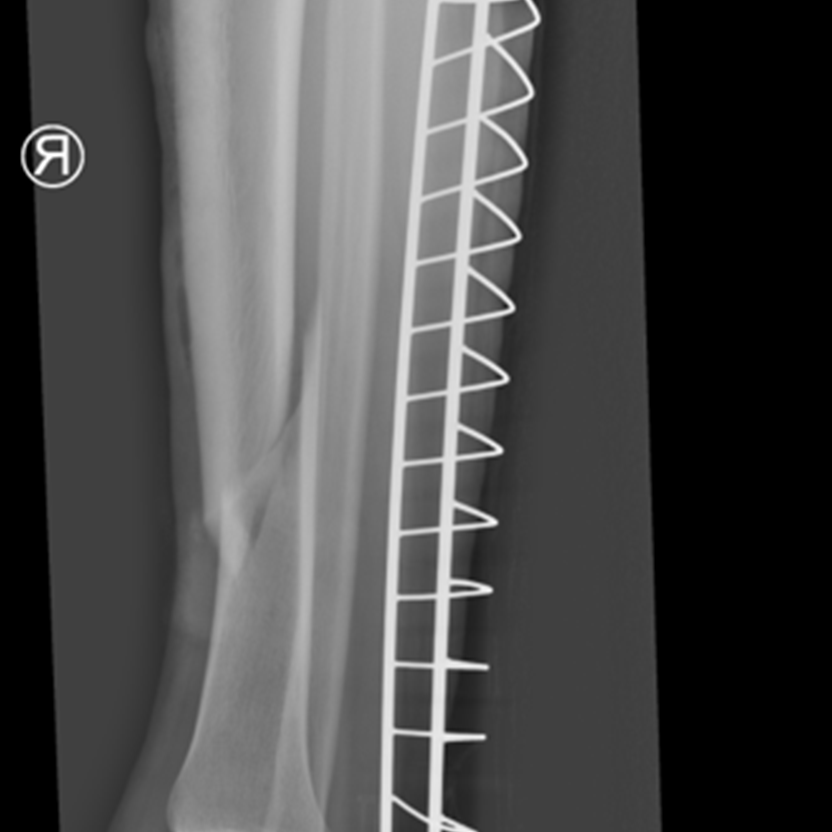

Jest obserwowany tylko w przypadku leczenia operacyjnego złamań i nie zachodzi w naturze. Do powstawania zrostu pierwotnego konieczna jest anatomiczna repozycja (nastawienie) złamania oraz stabilne zespolenie kości. Stabilne zespolenie to takie, które pozwoli wyłączyć wszystkie ruchy w miejscu złamania. Gdy takie warunki zostaną osiągnięte, następuje kaskada bezpośredniego gojenia kości-zrostu pierwotnego. W wyniku tego procesu możliwa jest bezpośrednia regeneracja kości do takiej samej struktury i budowy jak sprzed urazu, bez konieczności jakichkolwiek etapów przebudowy. Aby taki proces nastąpił, konieczne jest leczenie operacyjne i zespolenie kości przy pomocy płytek i śrub, bo tylko taki rodzaj zespolenia eliminuje niepożądane ruchy w miejscu złamania.

Przykład takiego zespolenia obrazuje zdjęcie 1.